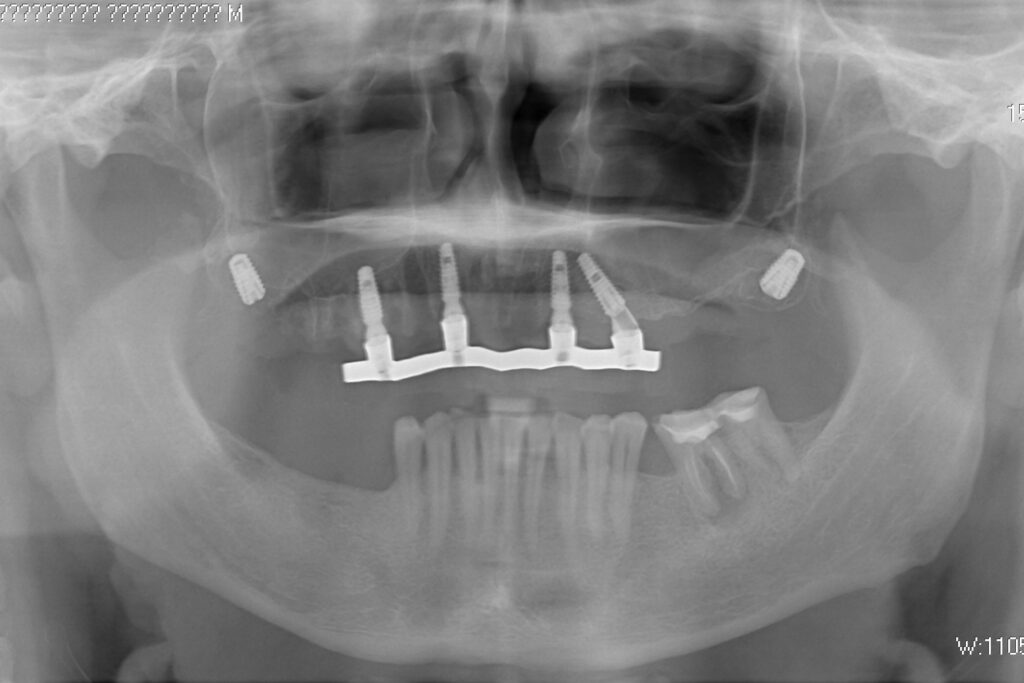

Жалобы: Пациент обратился к нам с целью проведения комплексной имплантации верхней челюсти.

Диагноз: Частичная вторичная адентия верхней челюсти.

После установки 6ти имплантантов Megagen Anyone, было принято решение зафиксировать металлоакриловый протез протез на 4 имплантата.

2 крайних имплантата, установленных в бугры, были ушиты с целью дальнейшего приживления. При постоянном протезирование протез будет зафиксирован на 6ти имплантатах.

Спустя 7 дней на верхней челюсти зафиксирован металлоакриловый протез из 12 зубов с опорой на 4 дентальные имплантата.